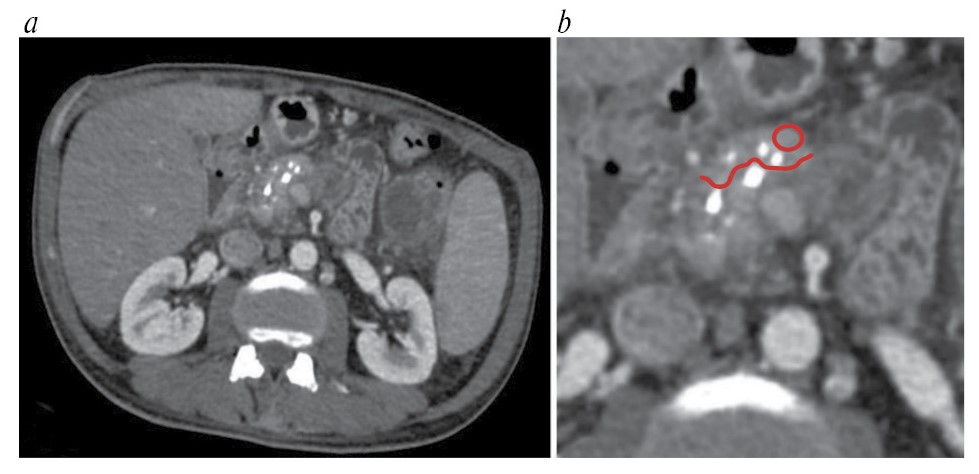

Значения рентгеновской плотности измеряли в участке ткани ПЖ площадью 0,2–0,8 см2 в области, подлежащей удалению в ходе операции. В случае новообразований при измерении отступали на расстояние 20 мм от края ново- образования для исключения из измерения зоны потенциальной десмопластической реакции (рис. 1). У пациентов с ХП измерения проводились в участке тканей, которые планировалось удалить в ходе резекционно-дренирующей операции (рис. 2). При этом участок для измерения выбирали таким образом, чтобы в него не входили кровеносные сосуды, патологические включения и образования, панкреатический проток и его боковые ветви, а также кальцинаты. В измеренных по данным МСКТ участках при патоморфологическом исследовании оценивали степень фиброза ПЖ.

Рис. 2. Пример измерения рентгеновской плотности ткани ПЖ у пациента с ХП. МСКТ в ПФ: а – томограмма в аксиальной плоскости; b – увеличенный фрагмент томограммы. Красной линией показана планируемая граница резекции, красным кругом – зона измерения.

Fig. 2. An example of measuring the X-ray density of the pancreatic tissue in a patient with chronic pancreatitis (CP). MSCT in the PP: a – axial plane; b – zoomed fragment of the tomogram. The red line shows the planned margin of resection, and the red circle indicates the measurement zone.